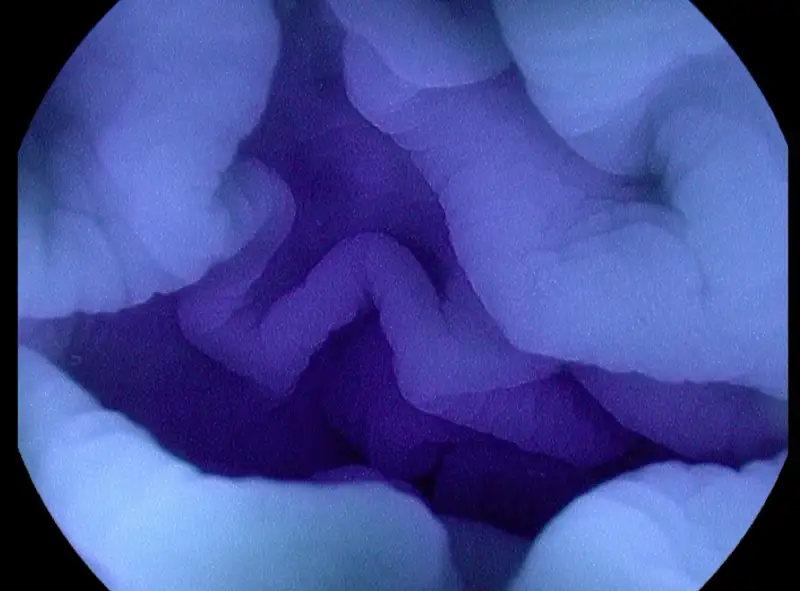

Dalam pembedahan, MB juga berfungsi sebagai pewarna bedah. Dokter menyuntikkannya ke area tertentu untuk: Menyoroti jaringan atau kelenjar getah bening. Ini membantu dokter melihat regio mana saja dari tubuh yang perlu diangkat atau diperiksa. Kemudian, MB juga berfungsi untuk mencari kebocoran pada jaringan. Jika ada bagian yang rusak atau bocor, MB akan merembes dan mewarnai area tersebut, sehingga dokter tahu persis dimana kerusakannya.